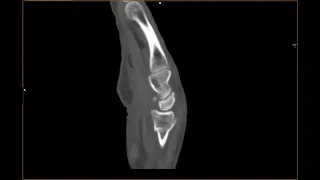

Video 2: reconstrucție sagitală din achiziție CT pumn sag

Discuţie caz nr 42: fracturile sunt diagnosticate clinic iar prin examinări radiografice și prin tomografie computerizată (CT) se pun în evidență: tipul de fractură, modificările de ax, prezența unor eventuale fragmente. Achiziția CT cu reconstrucție de volum este utilă în planificarea tratamentului ortopedic.

CT – Examen de elecție pentru bilanțul fracturilor. Performant în diagnosticul fracturilor oculte